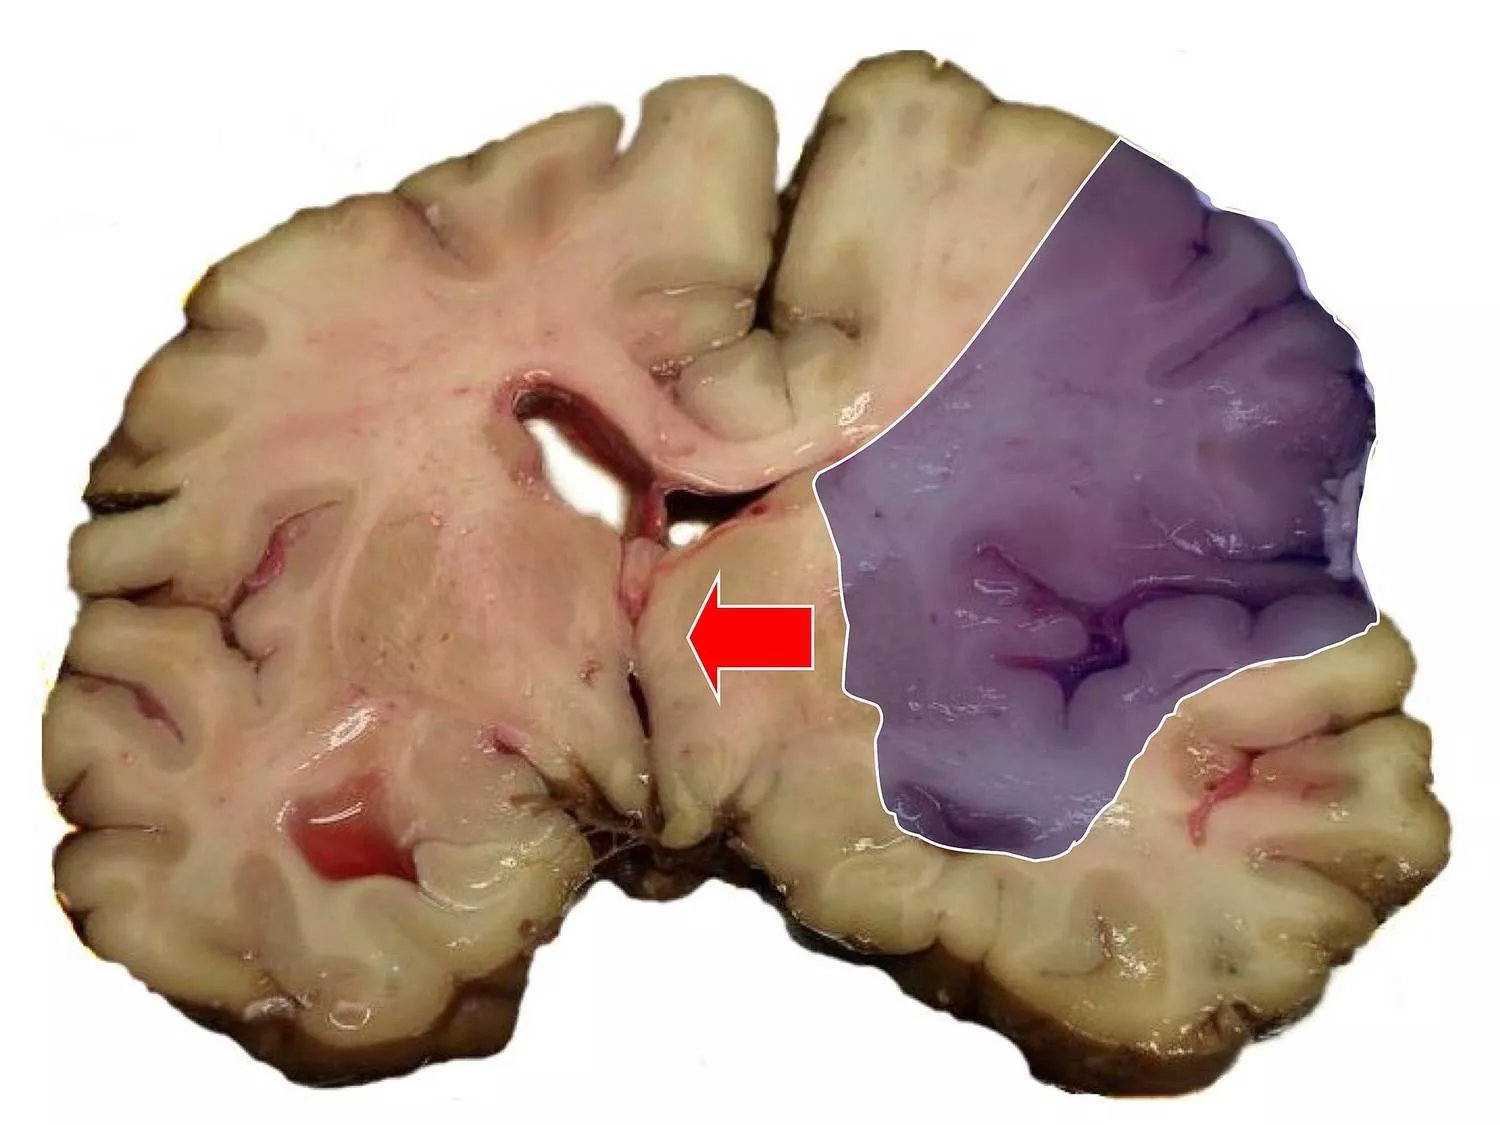

Iszkémiás sztrók boncolás utáni lelete. Középső agyi artéria elzáródásából fakadó stroke, színezve az érintett agyi terület, nyíllal jelölve a középvonali eltolódás.

Marvin 101; liszensz: CC BY-SA 3.0, Wikimedia Commons nyomán